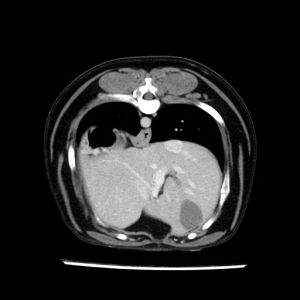

La lesione focale epatica , la ceus,la Tac e il chirurgo .